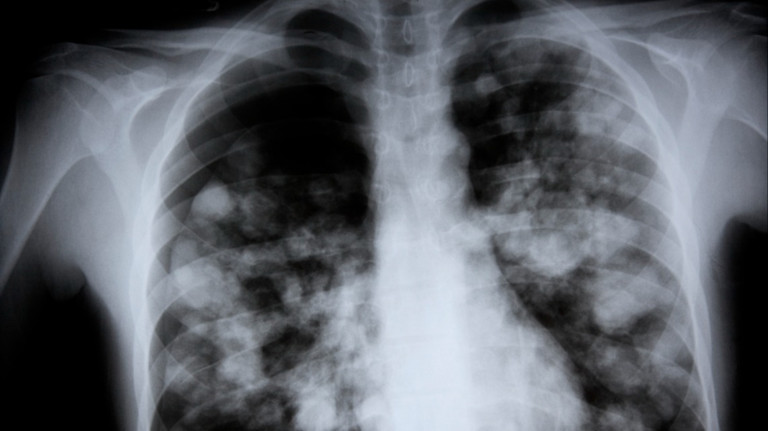

Pneumonia is a build-up of thick fluid in the small sacs of the lungs called the alveoli. It usually occurs in pockets throughout one or both lungs. This is called lung consolidation. It shows up fairly clearly on a chest X-ray.

Pneumonia can often be diagnosed with a thorough history and physical exam. Lung, blood, and sputum (what is coughed up) tests may also be performed.